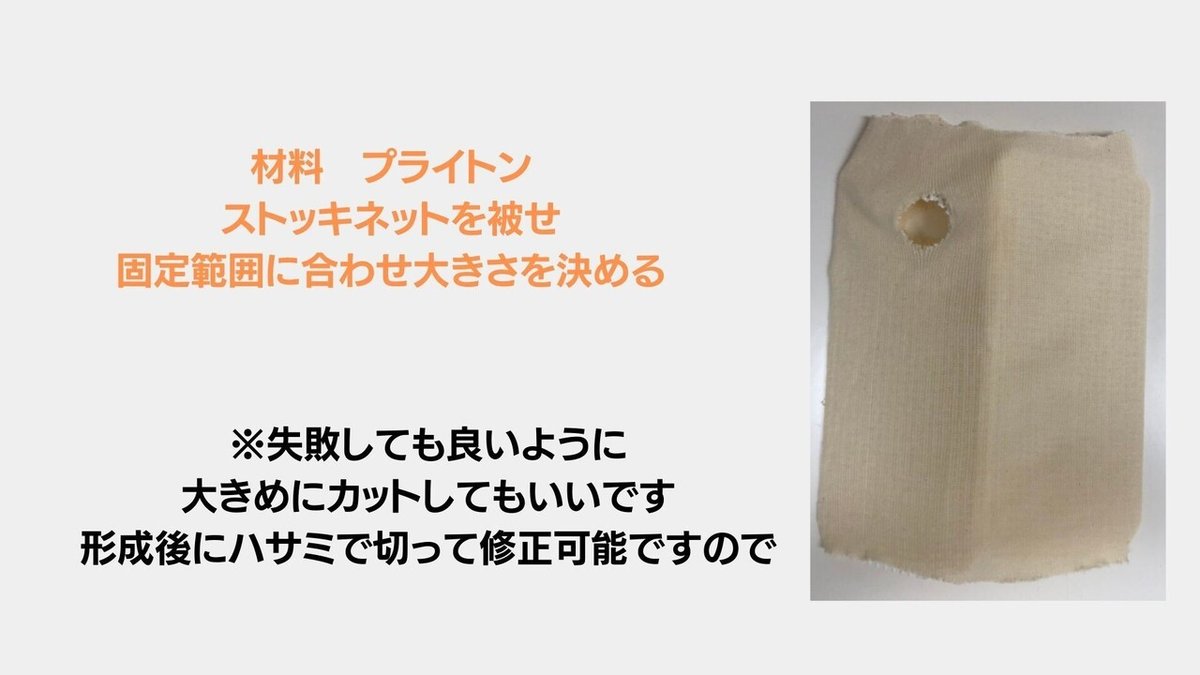

実践固定法

ここでは,私が接骨院時代にしていた

固定を紹介します

サムスピカ型 プライトンシーネを行いました

今回はプライトンシーネをご紹介します

固定の範囲は上記の通り

穴が開いてるのは気にしないでください